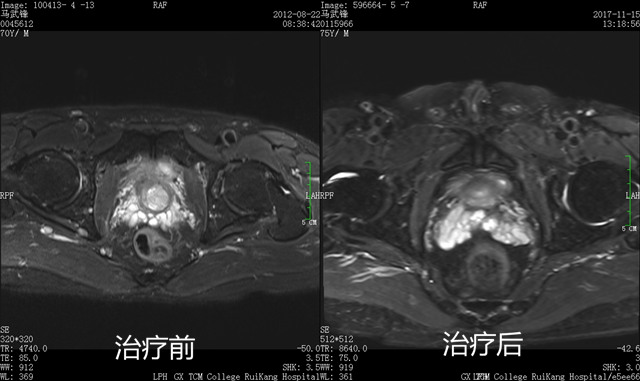

古稀之年的马先生2012年被确诊为前列腺癌,由于拒绝常规外科手术切除治疗,同年7月在瑞康医院接受了射波刀治疗,治疗后病情好转出院。8月时,马先生的复查肿瘤显示缩小,但继续服西药治疗时,仍有全身多处骨痛的情况,于是便改服中药调理。当时的马先生不仅全身骨痛,长期的病痛使马先生神疲乏力,体型消瘦,睡眠差,起夜多,梦多,活动后易出汗,同时怕冷易感冒,医院专家首诊辨证为:气虚血瘀,寒湿中阻,毒瘀内结,于是为马先生运用了健脾益气、温中化湿、化瘀散结、解毒抗癌的复法大方进行中医治疗。在连续服用药方两月后,马先生的精神及体力明显好转,疼痛消失,胃纳转佳,大便通畅,睡眠及易汗怕冷症状都得到了改善,极大地提高了生活质量,根据病情,便继续运用复法大方中药治疗,至今已逾5年半。现在,马先生每半年住院复查1次,病情稳定,影像学检查及生化检查均未见复发进展征象。一副中药,让饱受病痛折磨的马先生脱离苦海,也充分体现了发挥中医中药的抗癌效应具有积极意义。

马先生治疗后5年半,肿瘤吸收,无复发转移